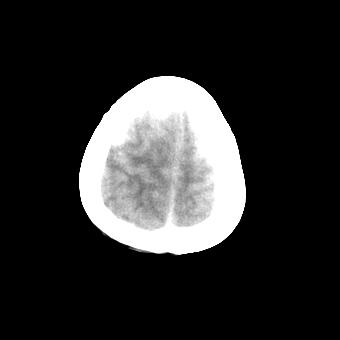

标题: CT16478:男 头晕 恶心 呕吐 [打印本页]

标题: CT16478:男 头晕 恶心 呕吐

病人不合作,图像质量差,右额叶及后纵裂可见高密度影,建议复查。

1.额叶显示密度不均匀,且右侧内见小片稍高密度影, 图像效果差些,不好定?

2.纵裂密度增高,部分脑回密度似乎也增高,蛛网膜下腔出血。

右额叶小片状高密度灶,周围有水肿带,为脑出血;是否有外伤史?若没有,则考虑肿瘤——胶质瘤出血可能性大。

病人不合作,图像模糊,大脑镰及纵裂池后部密度增高;考虑:蛛血?

右额叶片状低密度灶,其前内侧小片状略高密度,首先考虑胶质瘤

另外恶心呕吐多久,临床有无发热,年龄多大?不排除脑炎的可能

[quote]以下是引用叶子123在2008-11-13 9:55:00的发言:[br]患者因煤气中毒入院,临床及ct均诊断一氧化碳中毒性脑病[br][br]